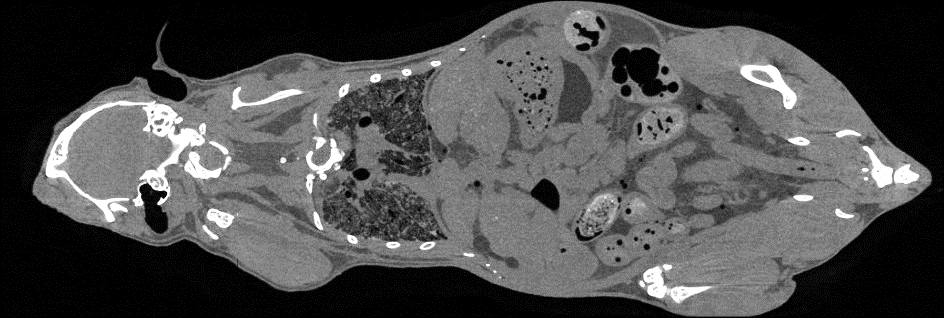

随着临床前研究向着活体成像、高分辨成像、多模成像等应用发展,传统的显微CT技术已无法满足生命科学领域的研究需求。近年来,基于光子计数探测器的能谱CT已成为当前CT新技术的重要发展方向,高分辨X射线能谱CT成像技术正在快速发展。在中科院装备研制等项目的支持下,项目团队研发出国际首台小动物活体能谱显微CT设备,通过以微米级分辨及多能谱图像再现动物体内的各器官组织的精细结构,实现动物实验从离体到活体、从黑白到彩色的进步,为生物医学研究提供更为先进的实验手段和科学仪器。

小动物活体能谱显微CT设备